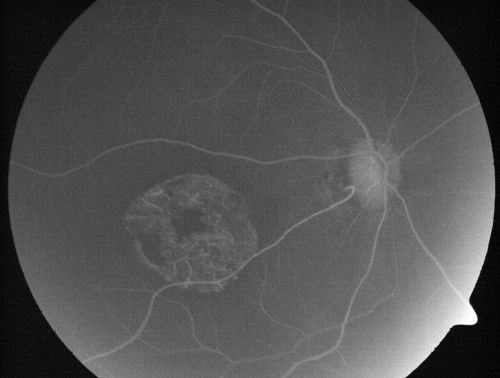

Stargardt's Disease - Macular Dystrophy - 69 Year Old African American Male - 20/200 both eyes

69-year-old man has had vision loss in both eyes starting 20 years ago. He was diagnosed at one point with Stargardt’s macular dystrophy. When I saw him, he had retinal atrophy in each eye.

Vision is 20/200 in each eye